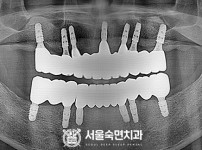

임플란트-전후사진1

임플란트-전후사진2

임플란트-전후사진3

임플란트-전후사진4